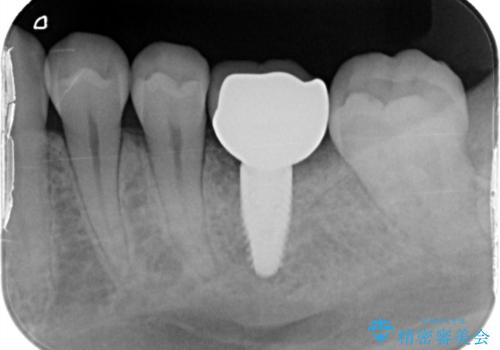

- 他院で抜歯と言われ、今後どうしたらいいのかを相談された患者様です。

抜歯を行った後は、Br、義歯、インプラント、何もしないという選択肢のメリットデメリットを説明させていただき患者様がインプラント治療を希望されたので今回治療させていただくことになりました。

歯のなかったところをインプラント治療を行うことによってまた噛める喜びを感じていただけて良かったと思っております。